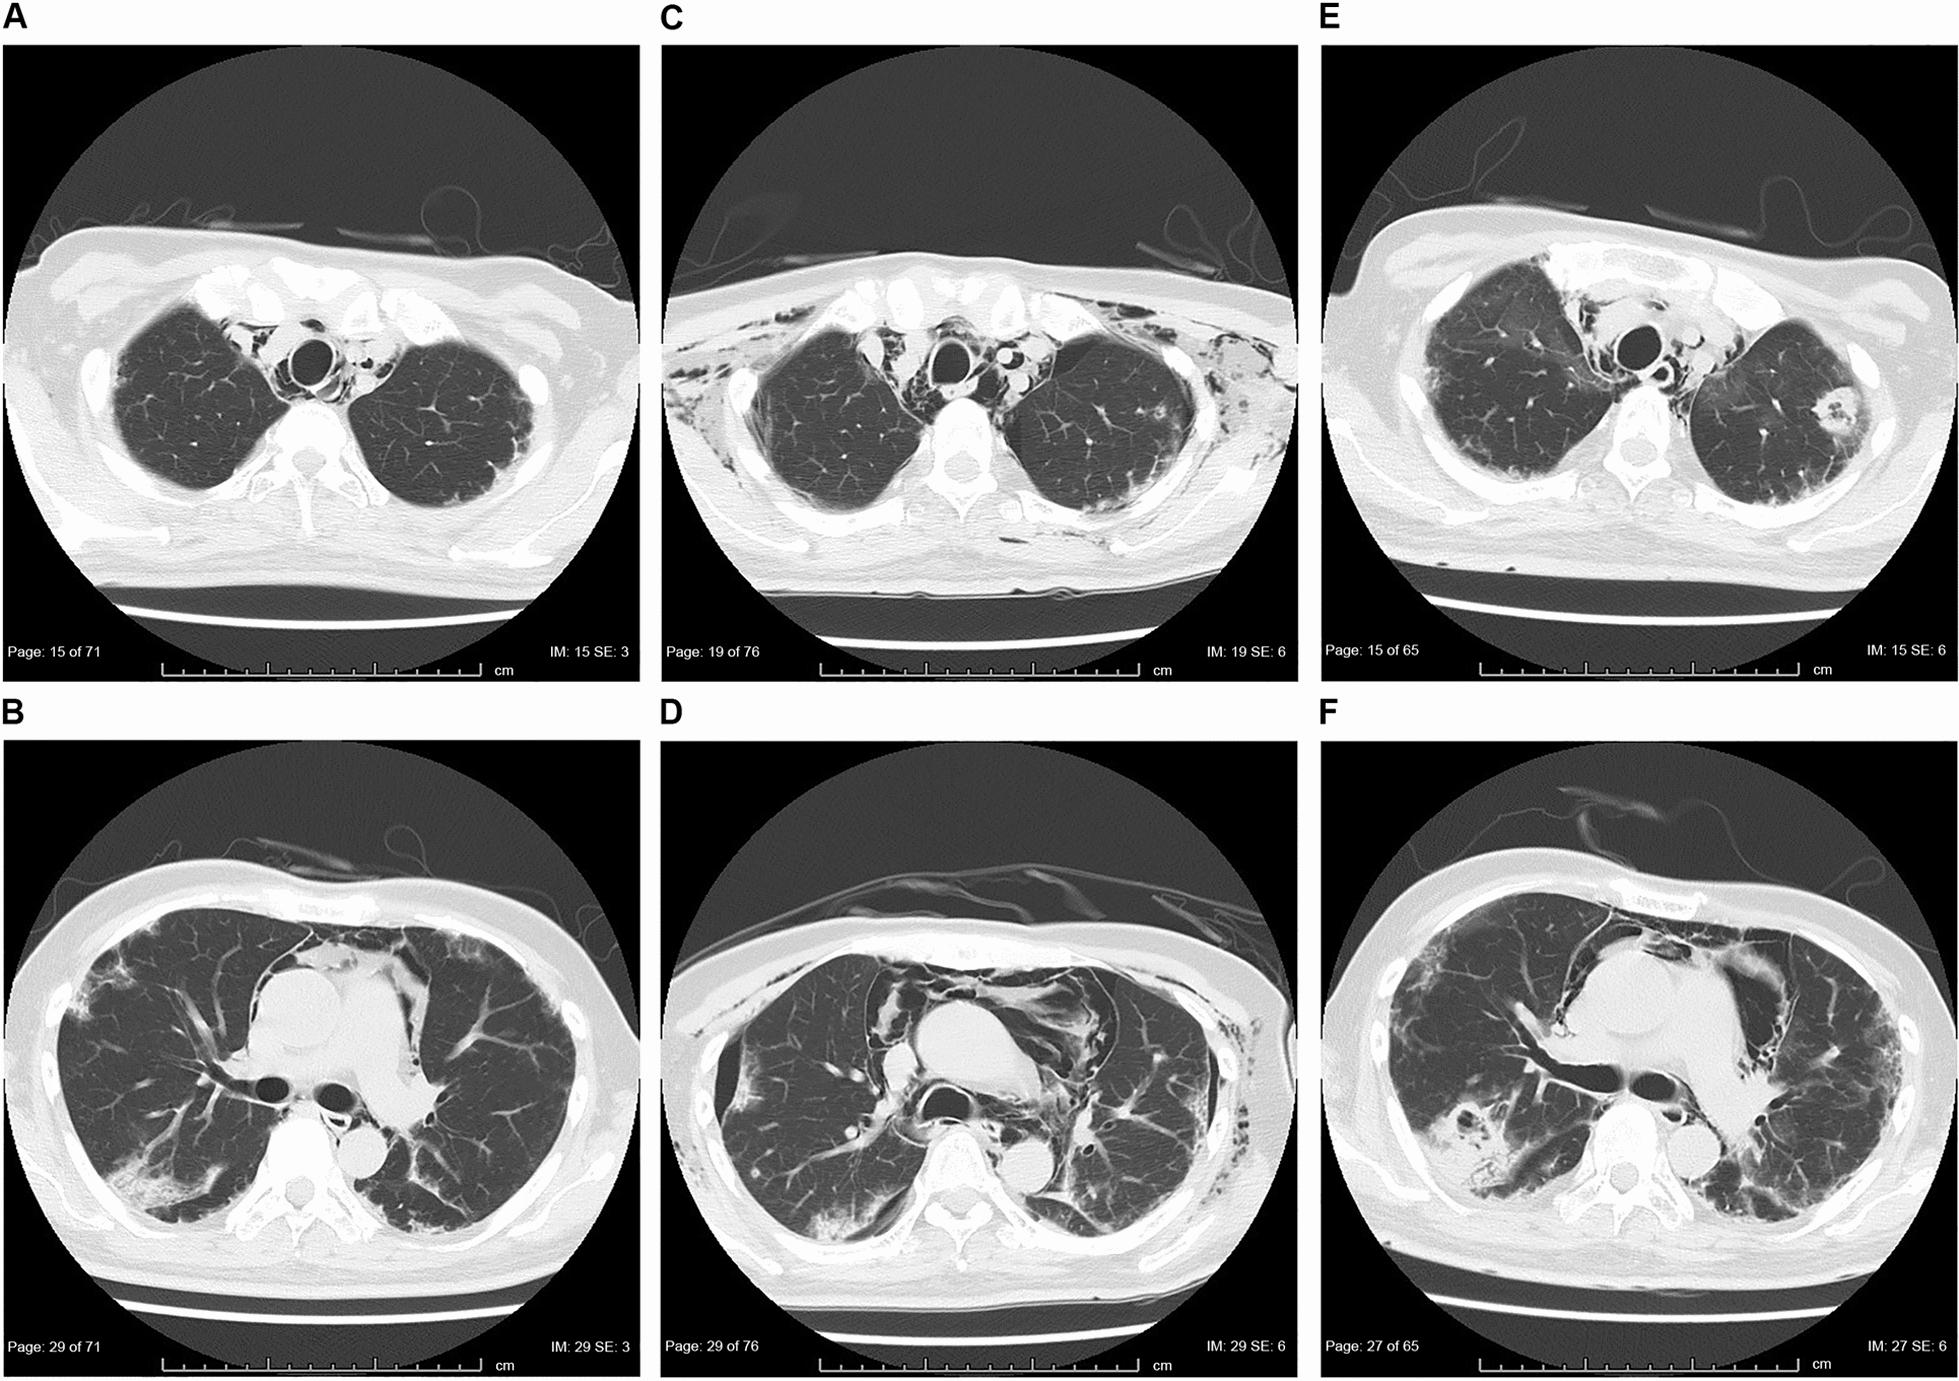

A 52-year-old Asian male patient presented with a chief complaint of dyspnea on exertion. He had a typical skin rash and rapidly progressive interstitial pneumonia. Additionally, anti-melanoma differentiation-associated gene 5 antibodies were detected; therefore, he was diagnosed with dermatomyositis-associated interstitial pneumonia. Respiratory failure worsened despite administering steroid pulse therapy, tacrolimus, and cyclophosphamide. Consequently, plasma exchange was performed on day 13 of admission. After a slight improvement, the patient's respiratory failure worsened. Thus, cyclophosphamide was replaced by tofacitinib on day 28. Although respiratory failure improved and the progression of interstitial pneumonia seemed under control, βD-glucan level increased and Aspergillus antigen was detected on day 49. Micafungin and voriconazole were administered, but the patient succumbed to worsening respiratory failure on day 61. The pathological autopsy revealed multiple nodular lesions with cavity formation in both lungs and the presence of Aspergillus with severe neutrophilic infiltration and necrosis, which supported the diagnosis of invasive pulmonary aspergillosis.

一名 52 岁亚洲男性患者以活动后呼吸困难为主诉就诊。他有典型的皮疹和快速进展性间质性肺炎。此外,检测到抗黑色素瘤分化相关基因 5 抗体;因此,他被诊断为皮肌炎相关间质性肺炎。尽管给予了类固醇脉冲治疗、他克莫司和环磷酰胺,但呼吸衰竭仍在恶化。因此,在入院第 13 天进行了血浆置换。在稍有改善后,患者的呼吸衰竭恶化。因此,在入院第 28 天将环磷酰胺替换为托法替尼。尽管呼吸衰竭得到改善,间质性肺炎的进展似乎得到控制,但β-D-葡聚糖水平升高,第 49 天检测到曲霉菌抗原。给予米卡芬净和伏立康唑,但患者在第 61 天因呼吸衰竭恶化而死亡。病理尸检显示双肺多个结节状病变伴空洞形成,存在曲霉菌,严重中性粒细胞浸润和坏死,支持侵袭性肺曲霉病的诊断。